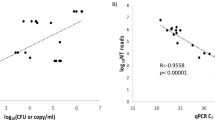

The RPM assay could discriminate and identify all the reference strains listed in Table 2 except for rhinovirus (RV). All the artificially synthesized DNAs, which represented unavailable positive samples, were mixed together and tested using the RPM; no cross-reaction was observed. The analytical sensitivity of the RPM assay was evaluated using serial 10-fold dilutions of in vitro transcribed RNA or DNA clones. The LOD ranged from 20 to 200 copies/reaction for mono-sample, and 20 to 2000 copies/reaction for mixed-samples (Table 2).

For HSV1, HSV2, VZV and CMV, the detection results by RPM-IVDC4 coincided with those obtained from the parallel q-PCR assays. For EV, EBV and HHV6, the RPM detection sensitivity was 100% and the RPM assay detected five more cases of EV infection, one more of EBV, and one more of HHV6 than by q-PCR (Table 3). In addition, the RPM assay detected 15 cases of JEV infection and one of MuV infection, which were not included in the q-PCR panel. For the aforementioned 23 cases not detected by q-PCR, true positives were confirmed by monoplex PCR followed by Sanger sequencing.

This study demonstrates that the RPM-IVDC4 platform can achieve highly-sensitive and specific detection of multiple CNS disease agents in a single test. A properly designed multiplex PCR strategy is essential to improve the performance of the RPM because the hybridization process is already standardized. The specificity test using 40 known positive samples demonstrated the capability of the RPM-IVDC4 to discriminate among different CNSI pathogens. As the primers and tiles for EV were designed according to the 5ʹ-untranslated region (UTR), the RPM could not discriminate RV from EV, which is the same situation as with the q-PCR assay. In our study, the use of TSP technology maintained target enrichment and mitigated amplification bias among different primer pairs. LOD experiments showed that the RPM-IVDC4 could detect as little as 20 copies/reaction of targeted genes, which is comparable to other reported methods and meets diagnostic requirements [14, 21].

Compared to q-PCR or other conventional methods, the main advantage of RPM- IVDC4 is the enablement of more comprehensive detection of CNSI pathogens. As shown in the Table 1, almost all common CNSI pathogens were included in the test menu of RPM-IVDC4, and some atypical/uncommon CNSI pathogens could also be detected by this method. By amplifying highly-conserved sequences using multiple primers, a greater number of positive cases could be detected with RPM than by q-PCR. For example, as variation in the 5ʹ-UTR is sufficient to allow accurate identification of groupings of EV [22], we designed 19 primer pairs specific to this region. As shown in Table 3, the RPM reported five more EV-positive cases than the equivalent q-PCR assay. Although both methods targeted the 5ʹ-UTR for EV detection, the 19 sets of primer pairs and probes in the RPM undoubtedly provided a greater probability of oligonucleotide matching than the one set (as is used in the reference q-PCR), resulting in higher clinical sensitivity for the RPM. Similarly, one more EBV, and one more HHV6, mistakenly defined as cases with unclear etiology by q-PCR, could be successfully identified by RPM. Thus, we conclude that the RPM array maximizes the likelihood of hybridization of primers to conserved regions within a given viral genus/family, demonstrating an effective strategy for detecting highly-variable or uncharacterized viruses.